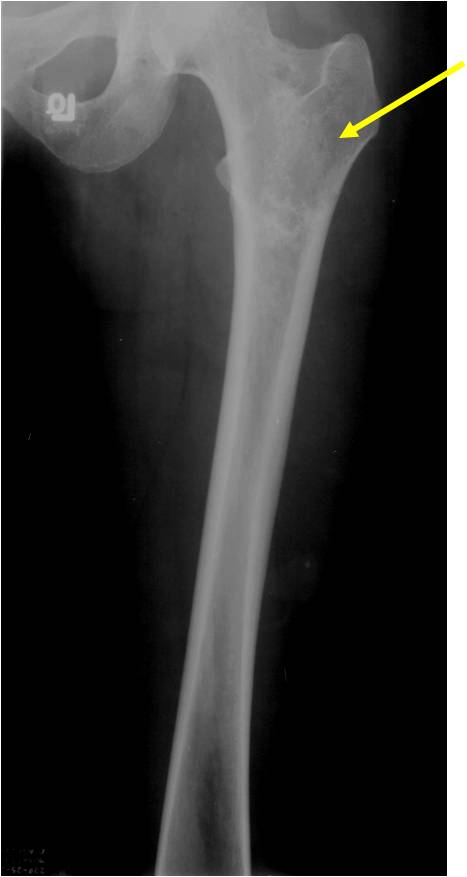

Ring and Arc Calcifications, Minimal Endosteal Scalloping, Cortex Intact, No Soft Tissue Component, No Periosteal Reaction

Minimal Endosteal Scalloping is Acceptable